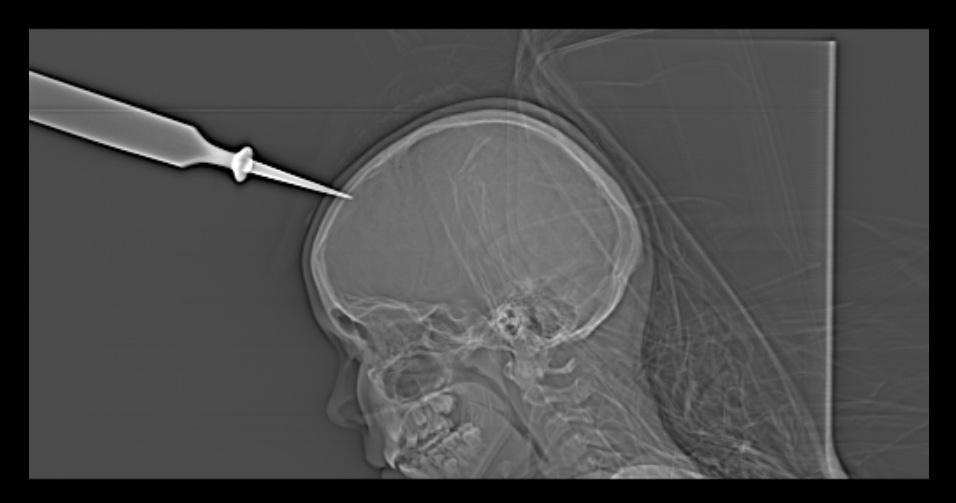

Da pasienten ankom sykehuset, var hun våken (Glasgow Coma Scale skår 15), og det var ingen påvisbare nevrologiske utfall. Det ble tatt CT caput (scout-bilde) i akuttmottaket. CT-undersøkelsen viste at tappjernet penetrerte kraniet (bilde), men det var ingen tegn til skade på parenkym eller noen intrakranial blødning. Tappjernet sto nær midtlinjen, og man fryktet skade av fremre del av sinus sagittalis superior, med potensiell blødningsrisiko. Pasienten ble tatt direkte til operasjonsstuen og lagt i narkose, og tappjernet ble fjernet. Spissen penetrerte så vidt dura, uten at det forelå skade på sinus sagittalis superior. Duradefekten ble reparert med et durasubstitutt (Duragen), og det ble gjort en kirurgisk revisjon av sårkanalen. Pasienten fikk tetanusprofylakse og antibiotikaprofylakse preoperativt. Postoperativt fikk hun antibiotika intravenøst i en uke. Det oppsto ingen komplikasjoner etter hodetraumet.